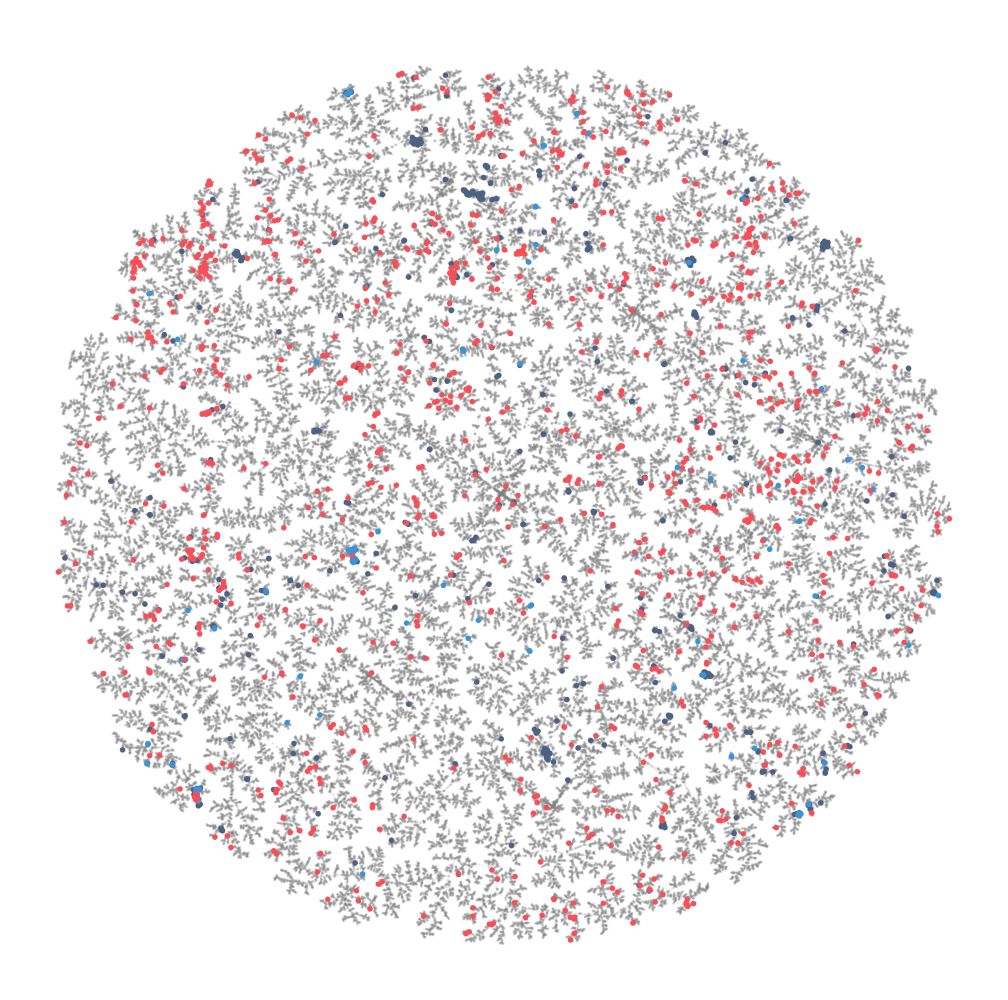

ArrePath’s AI/ML platform is at least 3X more efficient in identifying new compounds with progressible attributes than traditional approaches because:

- Our ML strategy combines data across disparate assays

- We conduct rigorous evaluation of models in real-world use cases

- Our AI is tightly integrated into the drug discovery process at all stages